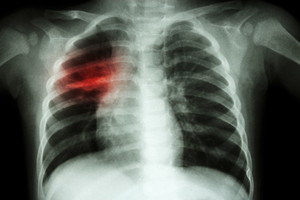

Pradiniai meningokokinės infekcijos simptomai dažnai yra nespecifiniai ir panašūs į peršalimo, tad net ir sveikatos priežiūros specialistui gali būti sunku diagnozuoti šią ligą ankstyvuoju etapu. Per pirmąsias 4–8 valandas kūdikiai gali būti mieguisti, neturėti apetito arba jų apetitas gali būti sumažėjęs, jiems gali pasireikšti karščiavimas, pykinimas, vėmimas, irzlumas ir kojų skausmas. Visais šiais simptomais gali skųstis ir vyresni vaikai. Klasikiniai simptomai, pavyzdžiui, kaklo sustingimas, šaltos rankos ir kojų pėdos, jautrumas šviesai ir hemoraginis bėrimas (raudonomis arba violetinėmis dėmėmis), atsiranda vėlesniuoju ligos etapu, tad gyvybę išsaugantis gydymas gali būti uždelstas.

Kūdikiai ir paaugliai priklauso padidintos rizikos grupei. Didžiausia rizika susirgti šia liga kyla kūdikiams. Meningokokinė infekcija gali būti gydoma antibiotikais, tačiau svarbu, kad būtų greitai pradėta gydyti1.